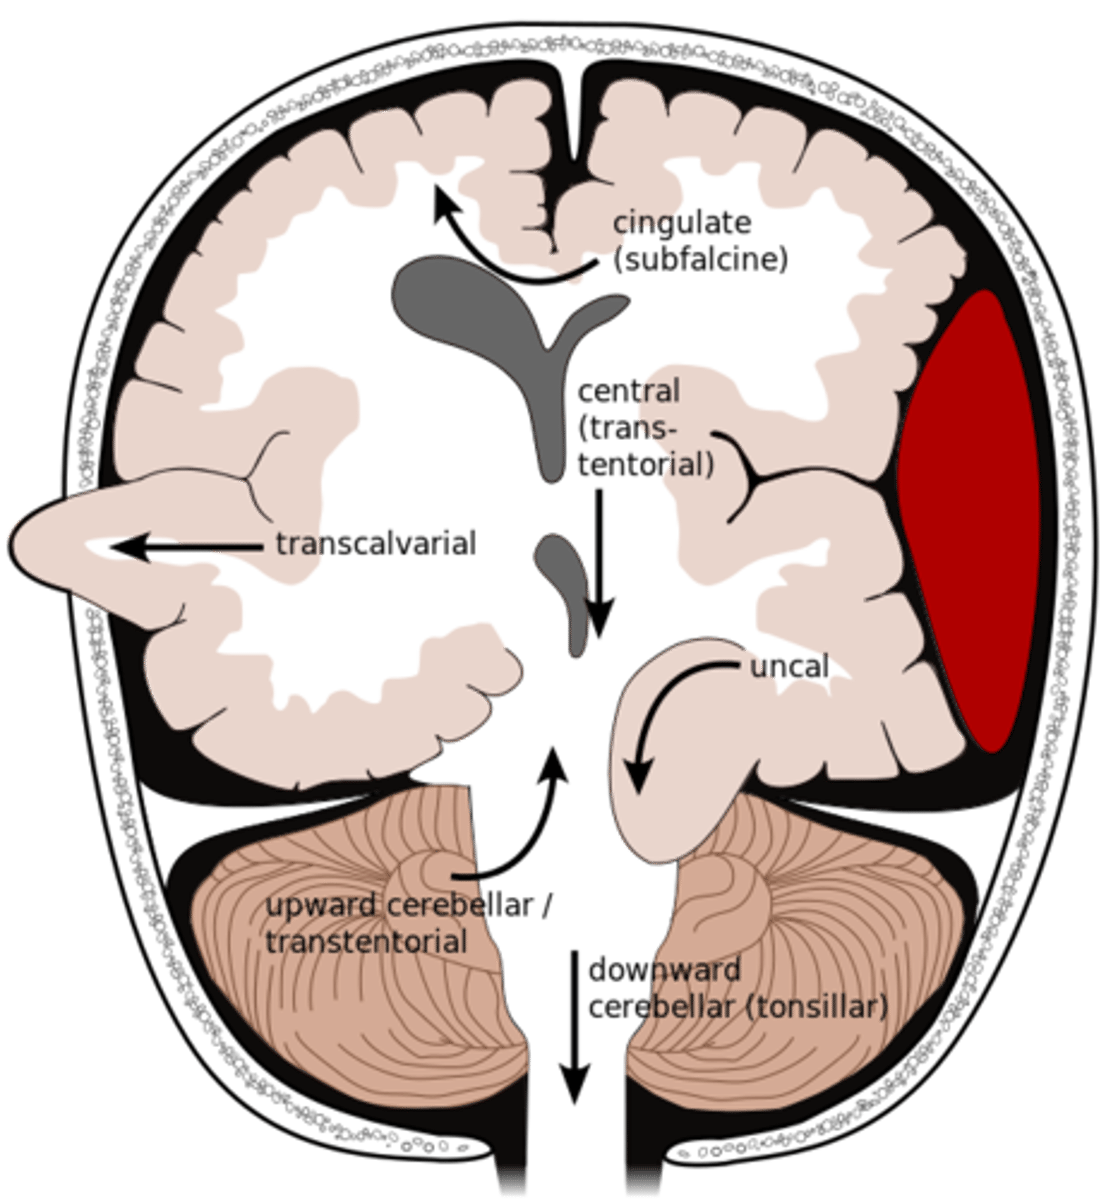

What is an uncal herniation?

most common.

unilateral lesions forces uncus of temporal lobe to displace and compress on the midbrain.

What is a central herniation?

Downward shift of cerebral hemisphere, compressing the brainstem

What is a cingulate herniation?

shift of brain tissue from one hemisphere to the other. Compress anterior cerebral artery.

Ischemic stroke may occur

What is a transcalvarian herniation?

brain begins to herniate outside of the skull. the brain will squeeze out of fractures, burr holes, or surgical incisions.

What is an upward herniation?

displacement of the cerebellum upward

What is a cerebellar Tonsillar herniation?

displacement of cerebellar tonsils downward this compressing the pons/medulla

s/s: alterations in resp. and cardiac functions- rapidly progressing to cardiac arrest, Headache and neck stiffness, reduced muscle tone